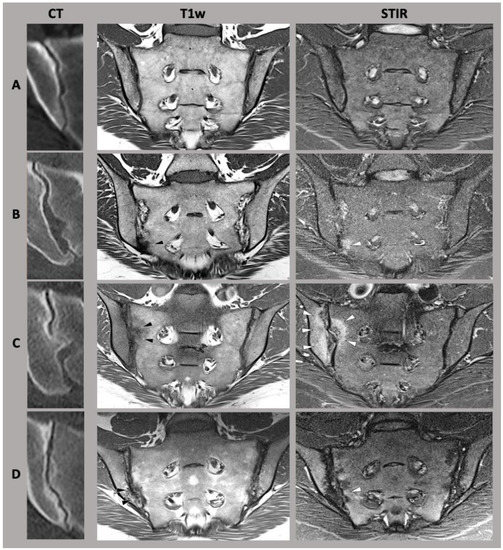

There is a well-established sexual dimorphism of the SIJ with consecutively more degenerative or mechanical stress-induced disease in the female SIJ [2]. In women, the ligaments of the SIJ are more flexible and the center of gravity is more ventrally located [8]. In the male pelvis, especially the inter-cristal measurement is larger than in the female pelvis [2]. The articular facet at the base of the sacrum for the 5th lumbar vertebra occupies more than one-third of the width of the base of the sacrum in males [2]. In females, this corresponds to less than one-third, whose sacrum is relatively wider [2]. In addition, the pelvic cavity is longer and more conically configured in males, whereas the female pelvic cavity is shorter and more cylindrical orientated [2], see Figure 2.

Figure 2.

Anatomy of the pelvis. A 3D computed tomography reconstruction. (A,C) Male pelvis. (B,D) Female pelvis. There is obvious sexual diamorphism in the pelvic anatomy. The male pelvic cavity is longer and more conically configurated with a longer and narrower sacrum, while the female pelvic cavity is narrower and cylindrically orientated.

The surface area of the sacroiliac joint is slightly larger in men than in women [26] with a typically thinner sacrocartilaginous alignment, suggesting a higher tolerance towards biomechanical load in men [2,16]. The SIJ in women is characterized by higher SIJ mobility [8], which is primarily enabled by a lower curvature of the SIJ surface in women. Correspondingly, these differences in sacroiliac joint anatomy lead to differences in biomechanical and biophysical properties with higher rates of SIJ misalignments in women [27]. This is also associated with an increased rate of lower back pain in female patients [28].